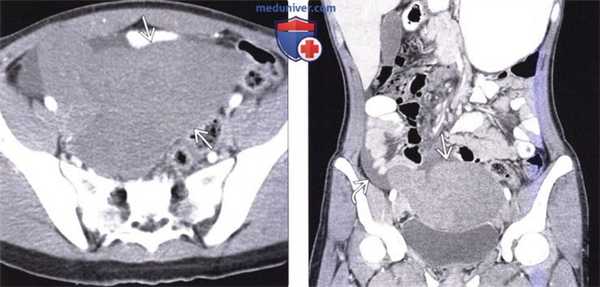

(Слева) На аксиальной КТ с контрастным усилением у ребенка с острой болью в животе определяется большое образование, не накапливающее контраст, в тазу.

(Справа) На корональной КТ с контрастом вновь визуализируется это же образование в тазу, определяется также жидкость возле образования с правой стороны. Обратите внимание, что в брюшной полости селезенка отсутствует. Во время операции обнаружился заворот и инфаркт «блуждающей» селезенки, находящейся в тазу, и сопоставимой с обнаруженным на КТ образованием. Нетипичная локализация селезенки обусловлена слабостью или отсутствием ее связочного аппарата.